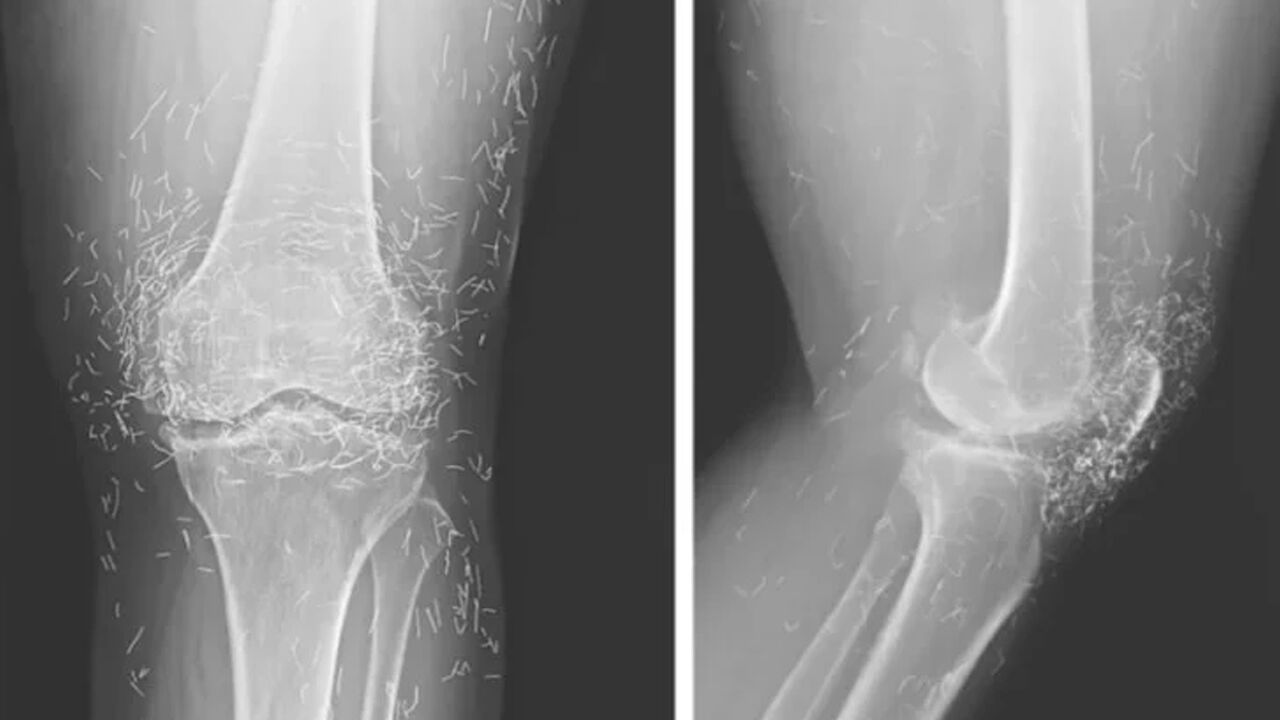

Hastanede yapılan tetkikler sonucunda, röntgendeki altın ipliklerin, kadının düzenli olarak uygulattığı altın iplik akupunkturu seanslarında bilerek bırakıldığı öğrenildi. Bu uygulamada steril kısa altın iplikler dokuya yerleştirilerek sürekli uyarım sağlanması amaçlanıyor.

Ayrıca bu ipliklerin görüntüleme teknikleri üzerinde de olumsuz etkileri olabiliyor. Röntgenlerde yorumlamayı zorlaştırmasının yanı sıra, manyetik rezonans (MR) görüntülemelerinde ipliklerin hareket etmesi ve damarlara zarar vermesi riski bulunduğu vurgulandı.

Doktorlar, bu tür geleneksel tedavi yöntemlerine başvuran hastalarda altın ipliklerin varlığının mutlaka göz önünde bulundurulması gerektiğini belirtiyor. Neyse ki ipliklerin röntgende rahatça görülebilmesi sayesinde konumları zamanla takip edilebiliyor.